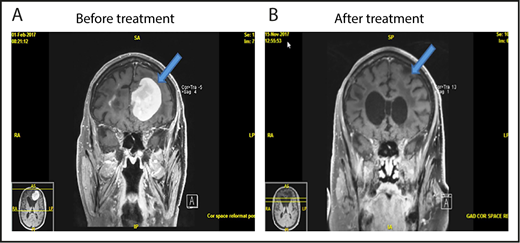

One patient had stable disease after 2 cycles and developed radiologic progression on brain MRI after 4 cycles without any significant clinical deterioration. She was taken off the study as per protocol. Brain MRI 1 month later without steroid or any other treatment showed improvement (Figure 4). This appears to be a case of pseudoprogression. She went on to have treatment with single-agent ibrutinib followed by ASCT and is currently in complete remission.

Pseudoprogression in a PCNSL patient treated with pomalidomide. (A-B) The patient had stable disease after cycle 2 and (C) showed radiologic findings suggestive of progression of disease on restaging MRI of brain after cycle 4 without clinical deterioration. She was taken off study as per protocol. (D) Repeat MRI of brain 1 month later without any steroid or any other treatment showed radiologic improvement. This case is the patient 11 on Figure 2.

We report the first apparent case of pseudoprogression/tumor flare in PCNSL related to IMiD. Although this was not confirmed by biopsy, the subsequent improvement on neuroimaging without steroid or any other treatment was consistent with this diagnosis. The possibility of pseudoprogression now needs to be considered in PCNSL patients after receiving IMiD. Future studies of immunotherapeutic agents such as IMiDs or checkpoint inhibitors should include option for continuation of treatment in these patients who are asymptomatic for additional 1 to 2 cycles before ascertaining true progression. Tumor flare has been previously reported in chronic lymphocytic leukemia and mantle cell lymphoma associated with lenalidomide.27,28